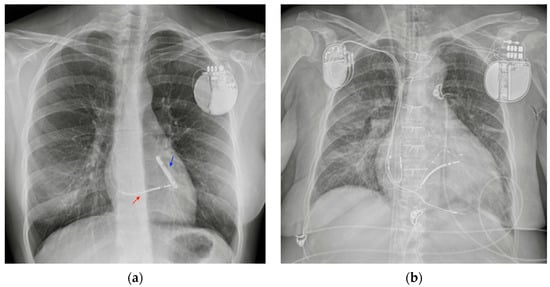

5.2. Pacemaker (PM) and Automatic Implantable Cardioverter-Defibrillator (AICD)

5.3. Ventricular Assistance Devices (VADs)